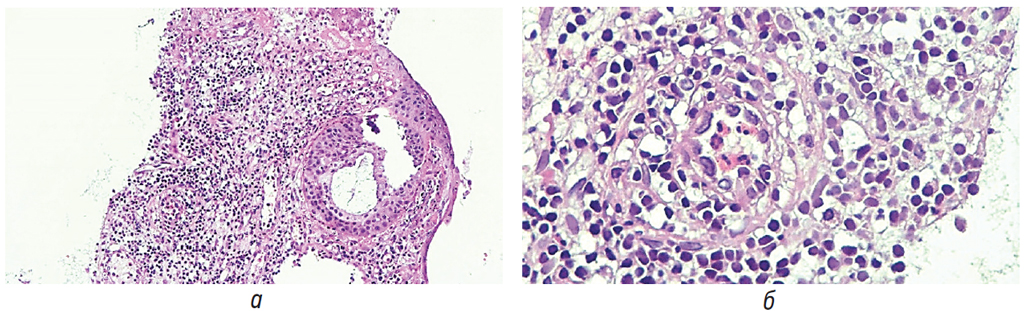

В апреле 2017 г. выполнена биопсия слизистой оболочки среднего носового хода с 2 сторон. При гистологическом исследовании слизистая оболочка была выстлана эпителием респираторного типа, с участком эрозивно-некротического поражения и выраженной лейкоцитарной экссудацией с примесью фибрина; краевой эпителий отличался распространенной плоскоклеточной метаплазией (рис. 3, а), участками склероза и гиалиноза субэпителиальных пространств. В области изъязвления определялась смешанная лимфоплазмоцитарная инфильтрация с примесью нейтрофильных и эозинофильных лейкоцитов, выраженная отечность стромы с расширенными сосудами. Отдельные сосуды венуллярного типа и единичные артериолы — с признаками продуктивного васкулита, большинство венул дилатированы; в просветах большинства — скопления эозинофильных лейкоцитов (рис. 3, б).

Рис. 3. а — эрозивно-некротическое поражение слизистой оболочки носа, распространенная плоскоклеточная метаплазия покровного эпителия; б — плотная лимфоплазмоцитарная инфильтрация слизистой оболочки носа, продуктивный васкулит с преобладанием эозинофильных лейкоцитов

В гистологическом заключении отмечена картина очагового язвенно-некротического поражения слизистой оболочки носа с признаками хронизации воспалительного процесса, продуктивного васкулита и выраженным эозинофильноклеточным компонентом воспаления.